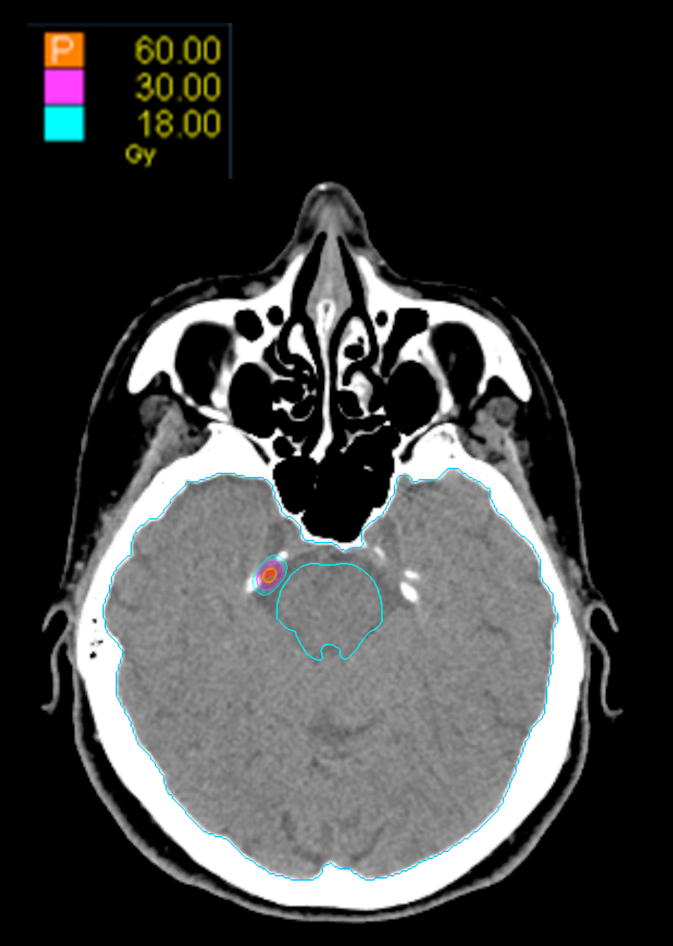

Treatment Plan Images

Treatment Planning Highlights

Fractionation

60 Gy in 1 fraction

PTV(s) Volume

PTV, 0.01cc

Dose Distributions

- Prescription to the 80 % isodose line

- Max. dose 75 Gy

Collimator

Fixed 5mm

Dose Calculation Algorithm

Ray-Tracing